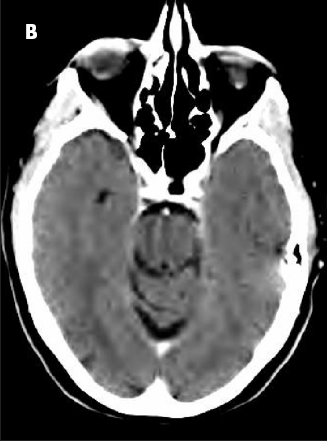

In this patient, treatment with R-CHOP chemotherapy for 6 cycles resulted in excellent clinical and radiological response (B).